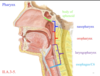

Identify the sections of the pharynx. Where is the pharynx located with regards to the vertebral column?

anterior to the vertebral column